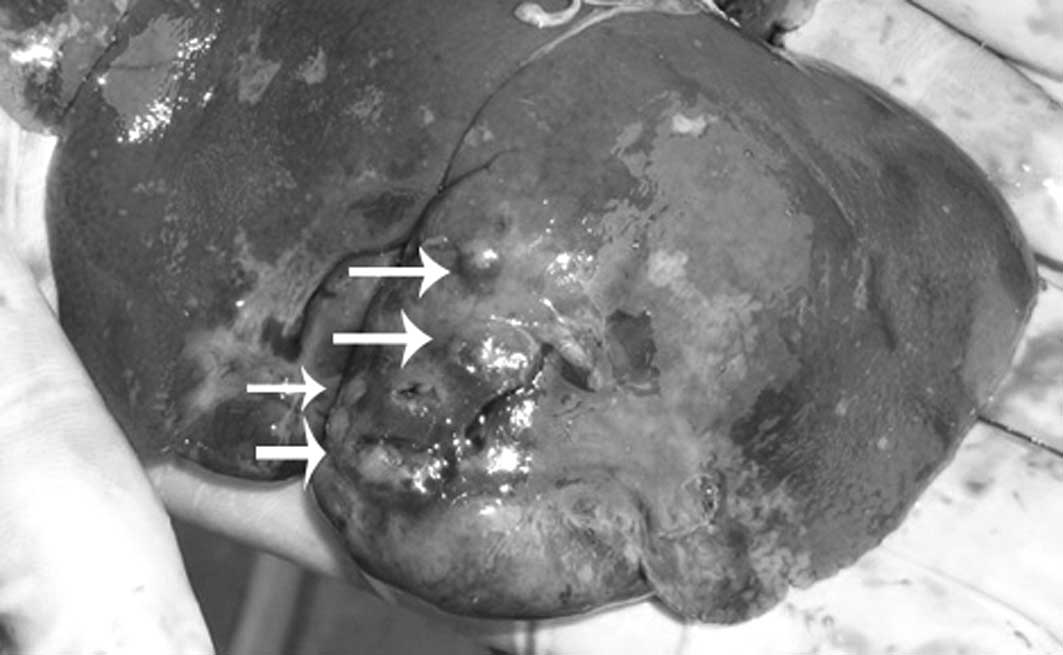

In group 1, 8 rabbits displayed no evidence of liver tumor growth at 2 weeks following implantation. Liver tumors were grown in 14 out of 22 rabbits with an overall success rate of 63.6%. In group 2, only 1 rabbit displayed no evidence of liver tumor growth. Successful liver tumor growth was achieved in 21 out of the 22 rabbits with an overall success rate of 95.5%. Upon further sub-analysis, single nodular tumors in the liver were observed in 4 out of 14 rabbits in group 1 (28.6%) and 14 out of 21 rabbits in group 2 (66.7%) (Figs. 2–5). Multinodular tumors in the liver were grown in 10 out of 14 rabbits in group 1 (71.4%) and in 7 out of 21 rabbits in group 2 (33.3%) (Fig. 6). In addition, extrahepatic metastases were observed in 5 out of 14 rabbits in group 1 (35.7%) and in 1 of 21 rabbits in group 2 (4.9%) (Fig. 7). There were statistically significant differences between the 2 groups. The overall liver tumor growth rate of group 1 was significantly lower than that of group 2 (P=0.025). Furthermore, the single nodular tumor growth rate of group 1 was significantly lower than that of group 2, and the multinodular tumor growth rate of group 1 was significantly higher than that of group 2 (P=0.041). Finally, a higher incidence of extrahepatic metastasis was observed in group 1 (P=0.028).